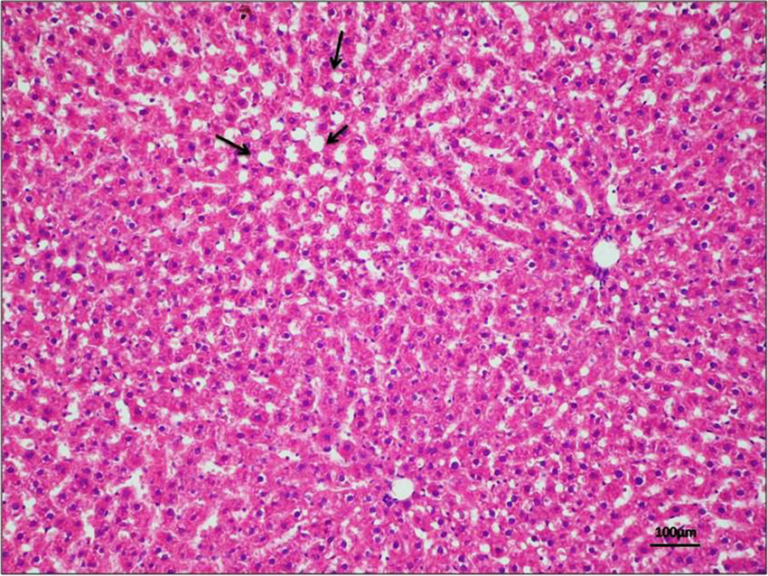

LIVER CELL EXAMPLES

Liver Cells:

Actually, (I realized this after I made the labeled photos) in the top photo here, the white spot is NOT a central vein, because that photo is taken with higher magnification than the very first photo. The white spot is probably a smaller vein or one of the sinusoids labeled in the first picture.

liver cells found in my slides:

This is pretty blurry, but I think this is about the same magnification as the very first picture. This is the only one that I could find so far. I will keep looking.